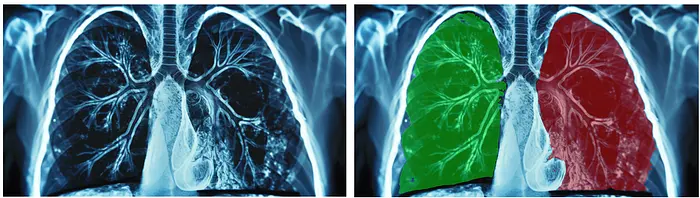

例如,在街景图像中,图像分割可以分离汽车、公共汽车、道路、建筑物和行人的像素,勾勒出每个对象的形状和边界。在医学成像中,图像分割可用于从牙科 X 光片中分离出单个牙齿,或从扫描图像中分离出心脏或肺部等器官,从而实现精确的测量和分析。

从下图可以看出 SAM-3 的性能,该图像被分割成“沙发”、“桌子”、“椅子”、“灯”、“地毯”和“植物”。每个分割对象都用不同的颜色显示(右图)。